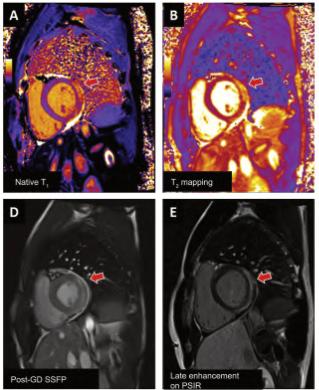

Lamiocarditisesunainflamacióndel músculodelcorazón(miocardio). Puedesercausadaporvariasenferme‐dades,infeccionesviralesobacterianas,tra‐stornosautoinmunitarios,exposiciónatoxi‐nas,entreotrosfactores.

¿CUÁLESSURELACIÓNCONLACOVID-19?

EnelcontextodelapandemiadeCOVID-19,se hainformadodecasosdemiocarditisaso‐ciadosalainfecciónporelvirusSARS-CoV-2. Secreequeestopuededebersealarespuesta inmunitariadelcuerpoalainfección,que puedeprovocarinflamaciónenvarios órganos,incluidoelcorazón.

Tambiénsehainformadodecasosmuyraros demiocarditisdespuésdelavacunación contraCOVID-19,especialmenteenpersonas jóvenesdespuésderecibirlavacunadeARNm (Pfizer-BioNTechyModerna).

Aunquesenecesitamásinvestigaciónpara comprendercompletamentelarelaciónentrela miocarditisylavacunaCOVID-19,losexpertos hanseñaladoquelosbeneficiosdelavacu‐

nacióncontraCOVID-19superanconcreces losriesgosdeefectossecundariosgraves.

Esimportantedestacarquelamiocarditises unaafeccióngravequepuedeponerenpeligro lavida,pueslamortalidadpuedellegaraserha‐stadel20%encasodenosertratadaatiempo, yelmétodonoinvasivomásadecuadoparasu diagnósticoeslacardiorresonancia.

Siexperimentasíntomascomodolorenel pecho,dificultadpararespirar,palpitaciones ofatigadespuésdelavacunaciónolainfec‐ciónporCOVID-19,debebuscaratenciónmé‐dicadeinmediato.

¿Porquéestáasociadaaunainfección ovacunadeCovid,SARS-CoV-2?Resonanciamagnéticaybiopsiaendomiocárdica